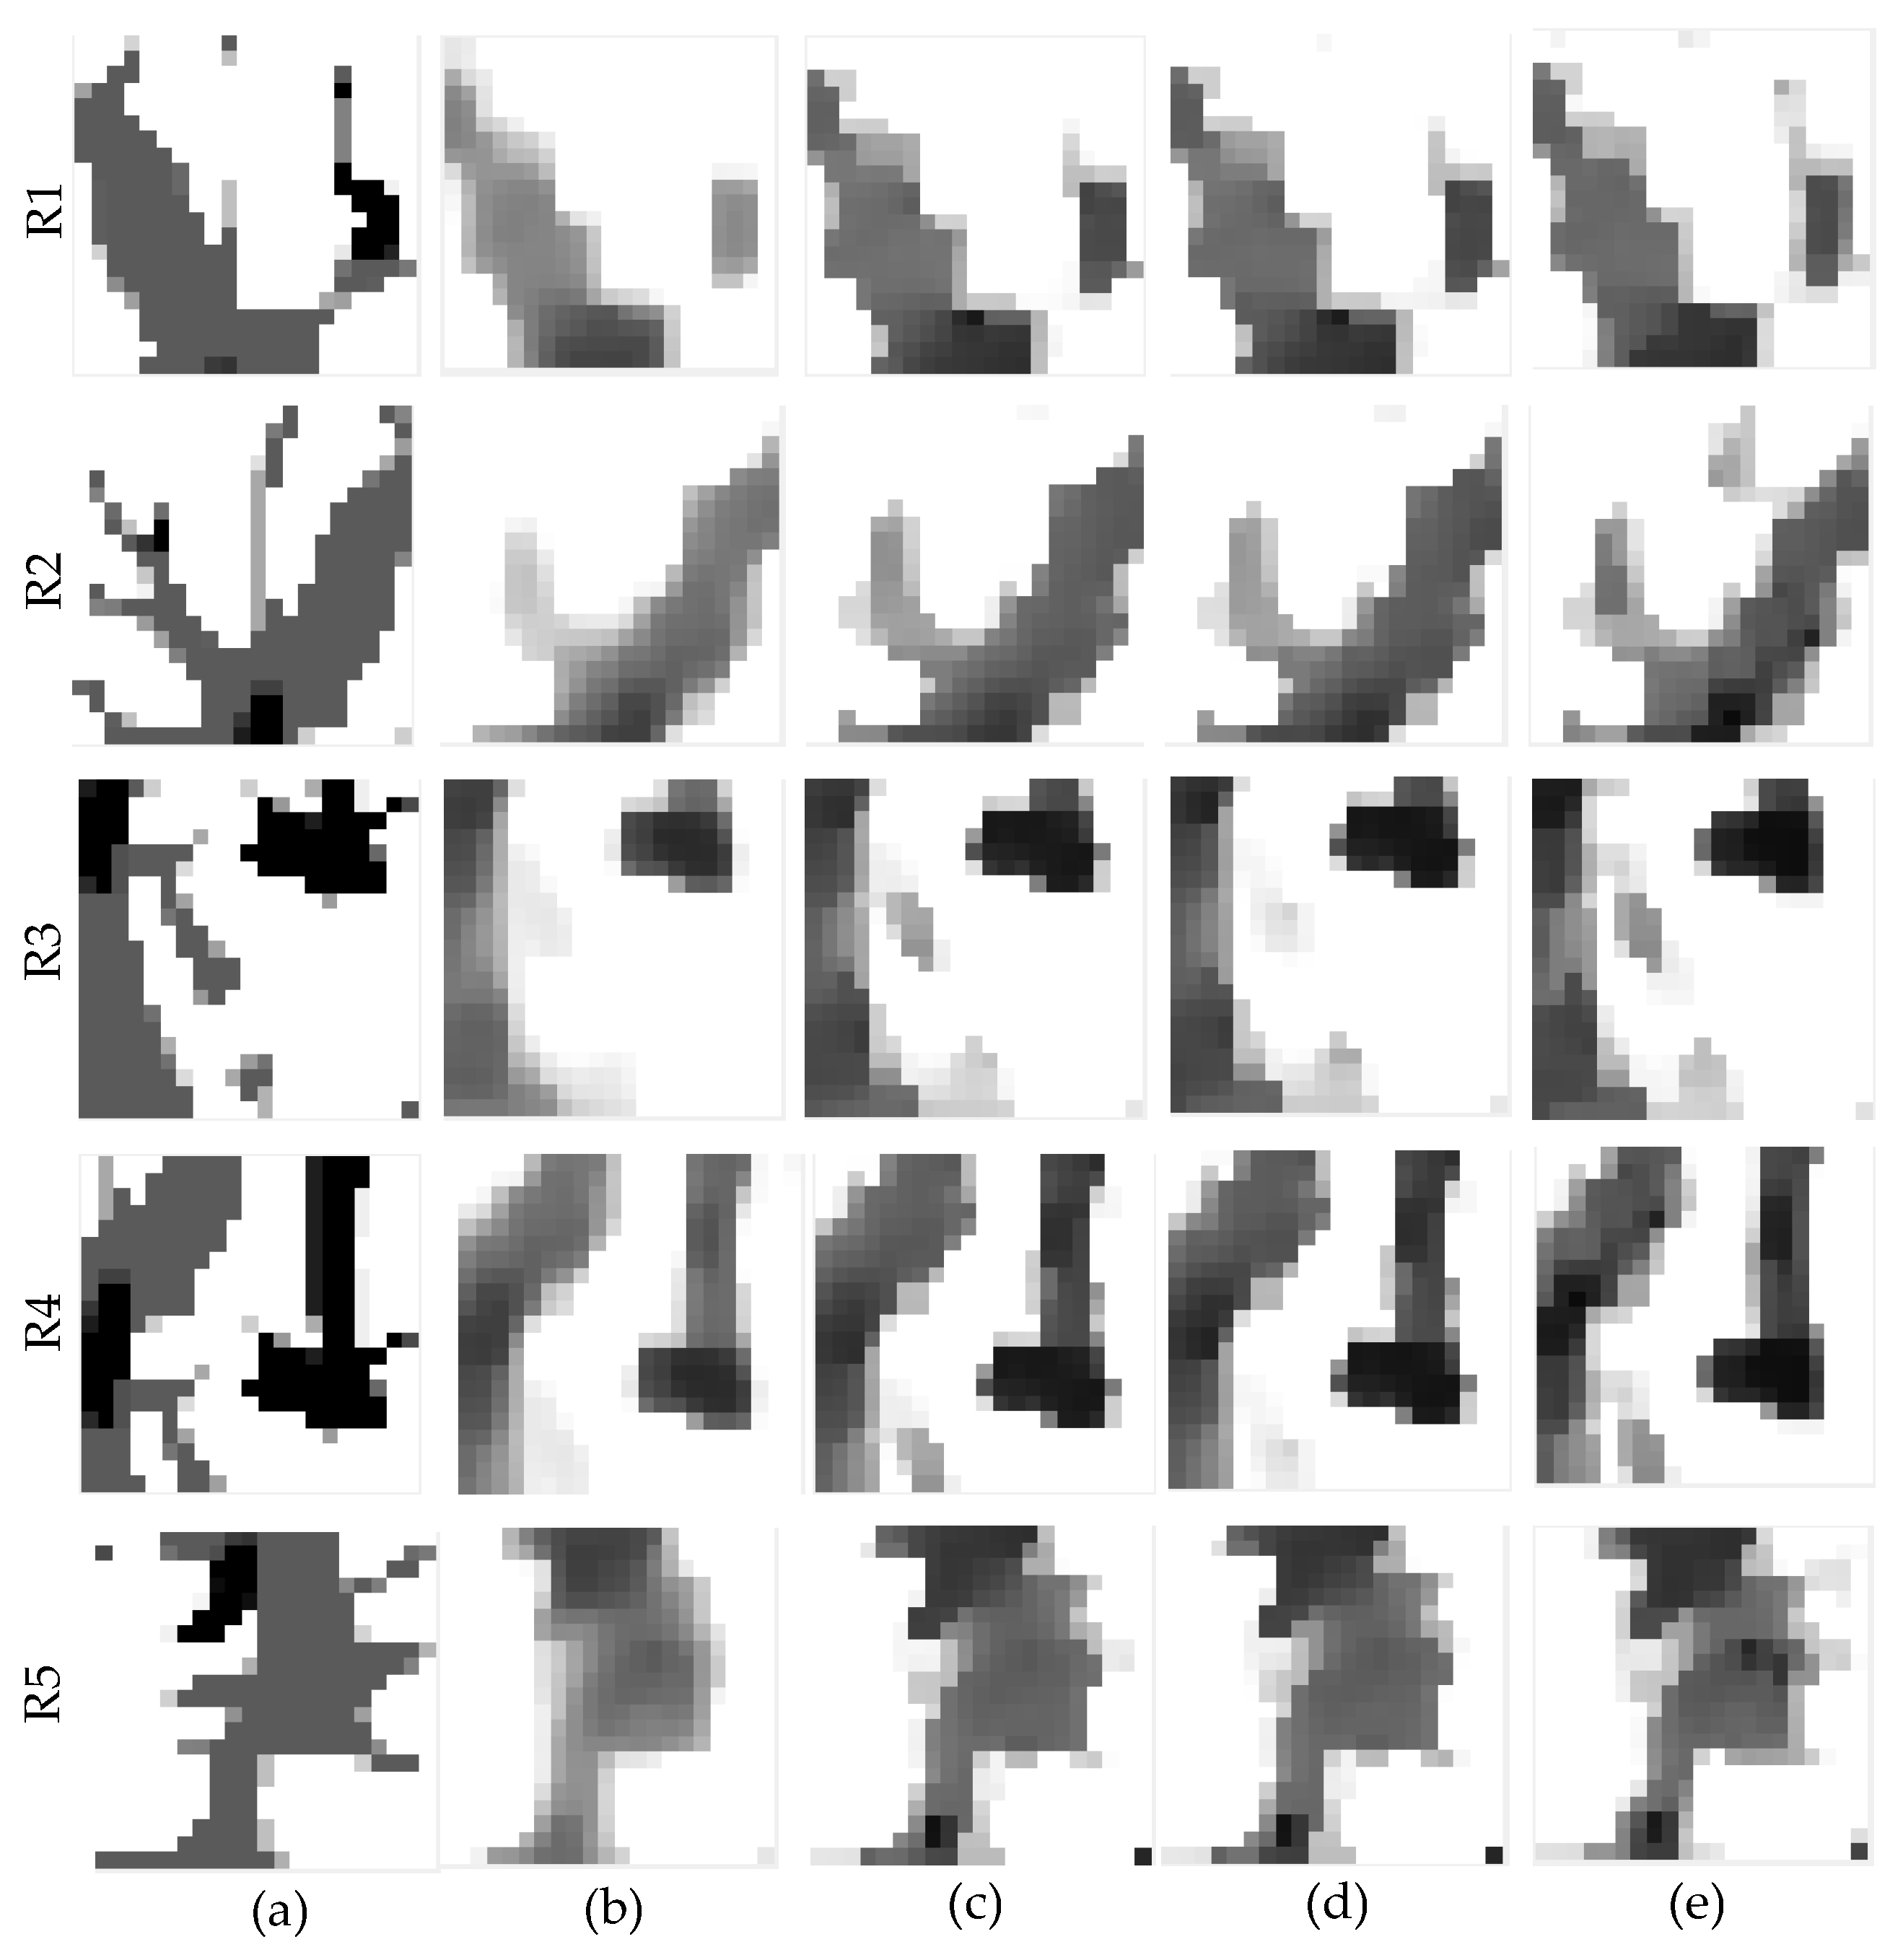

3.2. Qualitative Validation Using Physically Acquired Data